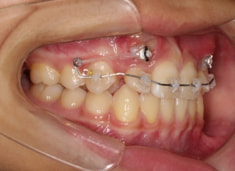

治療法:上顎急速拡大装置+クリアスナップ+フェイスマスク+上顎3番は開窓牽引CT写真にて位置確認

治療開始時

検査時のレントゲン分析では、上下顎の関係は、上顎の劣成長があり下顎前突傾向という値がでておりましたが、前歯ジャンプ後はフェイスマスクの効果もあり、上下顎の関係は正常化しています。

上顎が若干優位になっていますので、今後の下顎の成長のための貯金になっているくらいです。